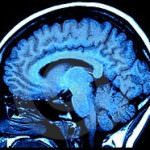

Gli scienziati USC hanno così lavorato con cuccioli di topi da laboratorio, modificati geneticamente per rendere visibile una proteina verde fluorescente quando il recettore TRPM8

(transient receptor potential melastasin 8) viene prodotto. Come spiegano gli studiosi, il recettore TRPM8 (noto anche come “recettore al mentolo”) è implicato nelle sensazione di

freddo, i famosi brividi.

Allora, l’osservazione dei topolini ha mostrato come i circuiti neurali fossero pienamente attivi solo 14 giorni dopo la nascita.

Spiega il professor McKemy: “Circa tre o quattro giorni prima della nascita dell’animale la proteina è già attiva. Tuttavia, gli assoni dei nervi che entrano nel midollo spinale

non sono completamente formati fino a due settimane dopo la nascita. Questo è coerente con le nostre osservazioni che indicano che il circuito [neurale] non è pienamente

sviluppato fin dopo la nascita. Quindi tutto ciò che disturba la formazione del feto in questa fase importante potrebbe avere effetti a lungo termine”.